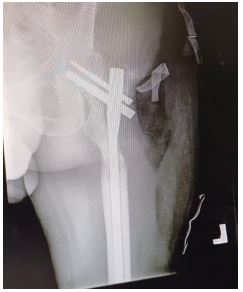

Case 1

Figure 1: (A) Anteroposterior view radiograph of the right leg showing comminuted fractures of the tibia and fibula. (B) Anteroposterior view radiograph of the right leg with intramedullary nail fixation of the fracture.